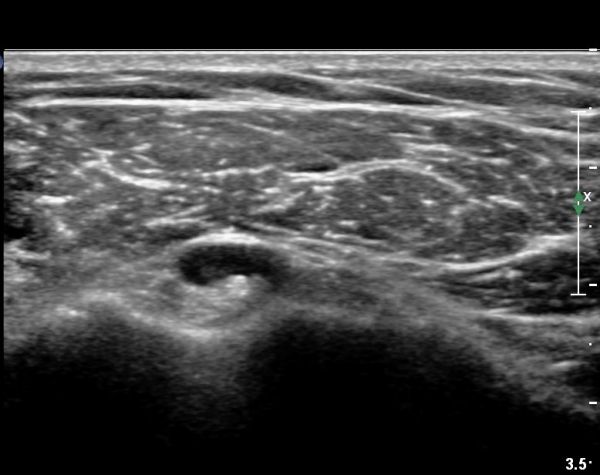

±Ø»ó°Ç Á¾´Ü¸é°Ë»ç¿¡¼­ ±Ø»ó°Ç³» ¼®È¸È­ À½¿µÀÌ °üÂûµÈ´Ù(»çÁø 4).